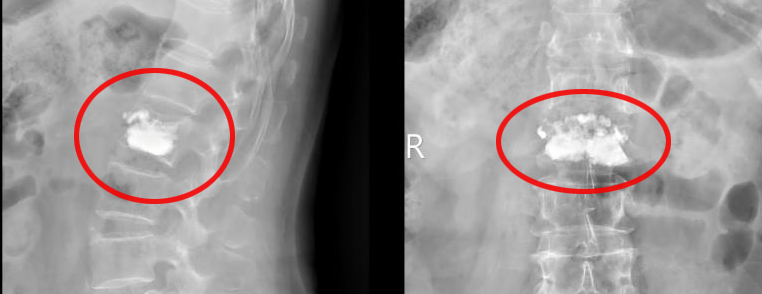

“别担心,微创就能解决眼下的疼痛。” 陈吉主任中医师的话给王阿姨吃了定心丸。随后,她接受了微创椎体成形术—— 在局部麻醉和影像引导下,脊柱骨科团队只用一根细针,就能向骨折的腰椎里精准注入 “骨水泥”。这种特殊材料迅速凝固,像给腰椎撑起 “内部支架”。

图片

整个手术仅用时 20 分钟,术后 3 小时,困扰她的剧痛就基本消失,当天就能佩戴腰围在家人协助下站立行走。

▲手术伤口仅有1厘米